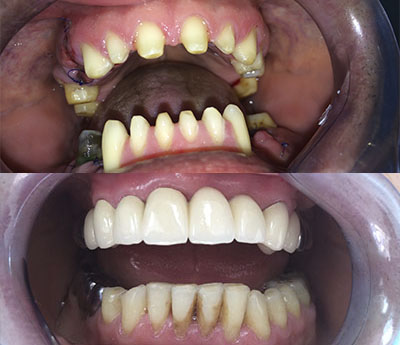

Puntea dentară este cea mai căutată soluție de umplere a spațiilor lipsă a danturii. Asta pentru că timpul de realizare este minim. Puntea este fixată pe dinții învecinați care, pentru o susținere mai bună, inițial sunt șlefuiți. Odată aplicată dantura capătă un aspect estetic natural și, dacă este întreținută corespunzător, are o durată de viață îndelungată.